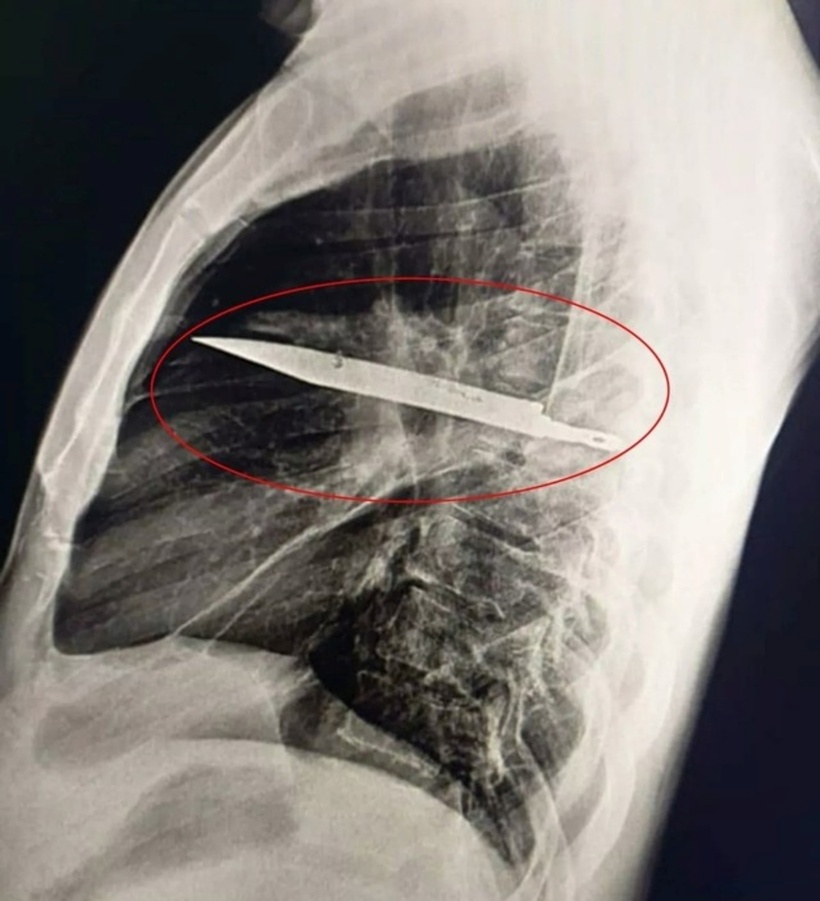

Hình ảnh chụp X-quang con dao trong cơ thể bệnh nhân. Ảnh: Journal of Surgical Case Reports.

Các bác sĩ sau đó bất ngờ khi kết quả chụp X-quang ngực cho thấy có một lưỡi dao lớn găm vào ngực anh này. Dựa trên hình ảnh phim chụp, con dao cắm sâu vào xương bả vai phải bệnh nhân và kỳ diệu thay nó không đâm vào các nội tạng quan trọng.